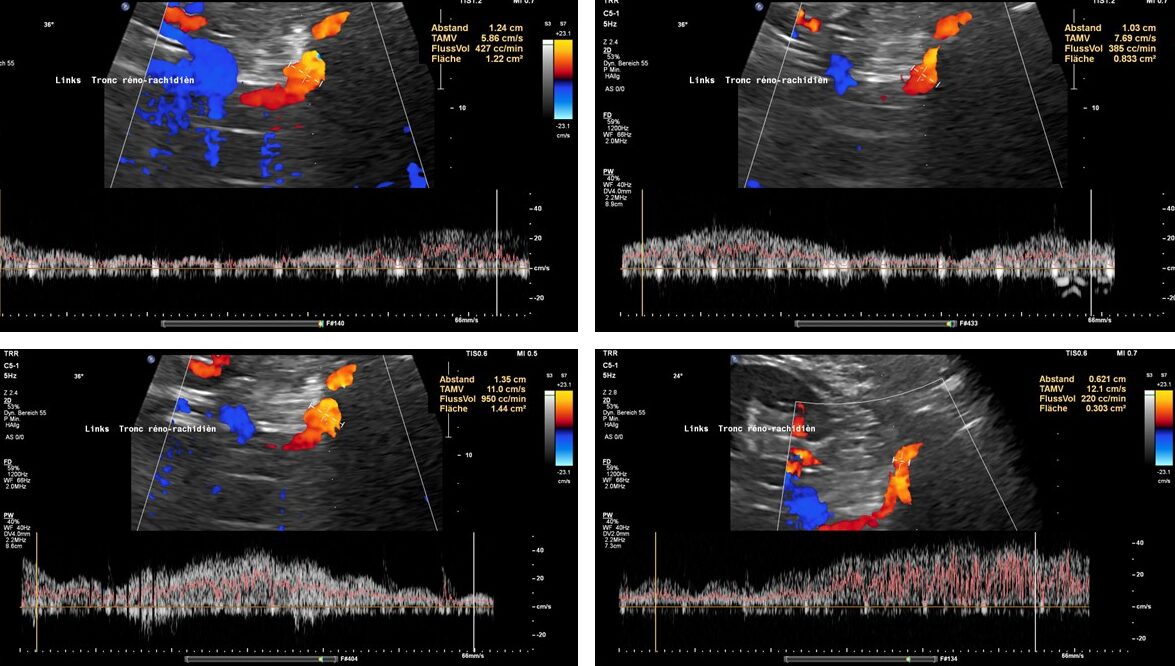

These images, taken from the front of the patient, show the tronc réno-rachidièn. This vessel runs in a U-turn along the left side of the lumbar spine towards the back, entering the intervertebral foramen and thus putting pressure on the spinal canal. They demonstrate that the preaortic portion of left renal vein (yellow dashed arrow) does not carry any blood, meaning that all of the left renal venous blood must be diverted via the tronc réno-rachidièn. The other natural collateral pathway, the left ovarian vein, is less significant here. In this patient ( as in many arteries with left renal vein compression) , the collateralisation via the left ovarian vein towards the pelvic venous circulation is obstructed by compression of the left common iliac vein. This combination is very common and requires simultaneous treatment of both the left renal vein and the left common iliac vein in one operation, by shielding both with a PTFE shield.

Blood within the tronc réno-rachidièn is modulated in a pulsatile manner, demonstrating rhythmic compression of the left renal vein between the aorta and superior mesenteric artery. This compression is so pronounced that no blood flow is visible ventral to the aorta only the pressure wave is transmitted towards the collateral vessel.

This image demonstrates the transfer of the pulsatile pressure of the aorta and the superior mesenteric artery towards the tronc réno-rachidièn (yellow arrows). Both arteries completely squeeze the final portion of the left renal vein obstructing the entire blood flow, but the pressure is rhythmically transferred towards the spinal canal and thus the spinal cord. Not rarely affected patients develop headaches and migraines which was not the case in this patient.

These images show the respiratory variability of volume transport within the tronc réno-rachidèn.